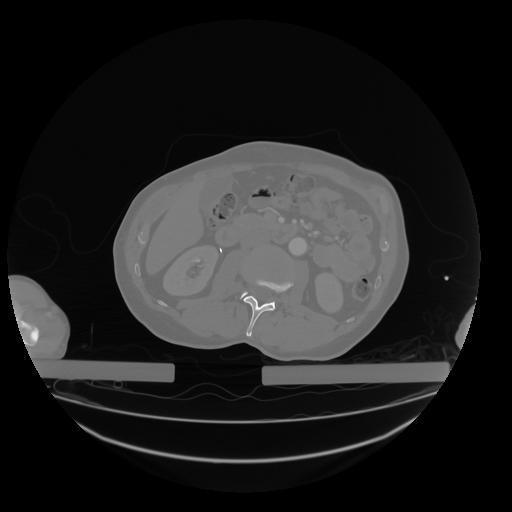

28 CUERPO,CE,Vol,2.0,CUERPO,,